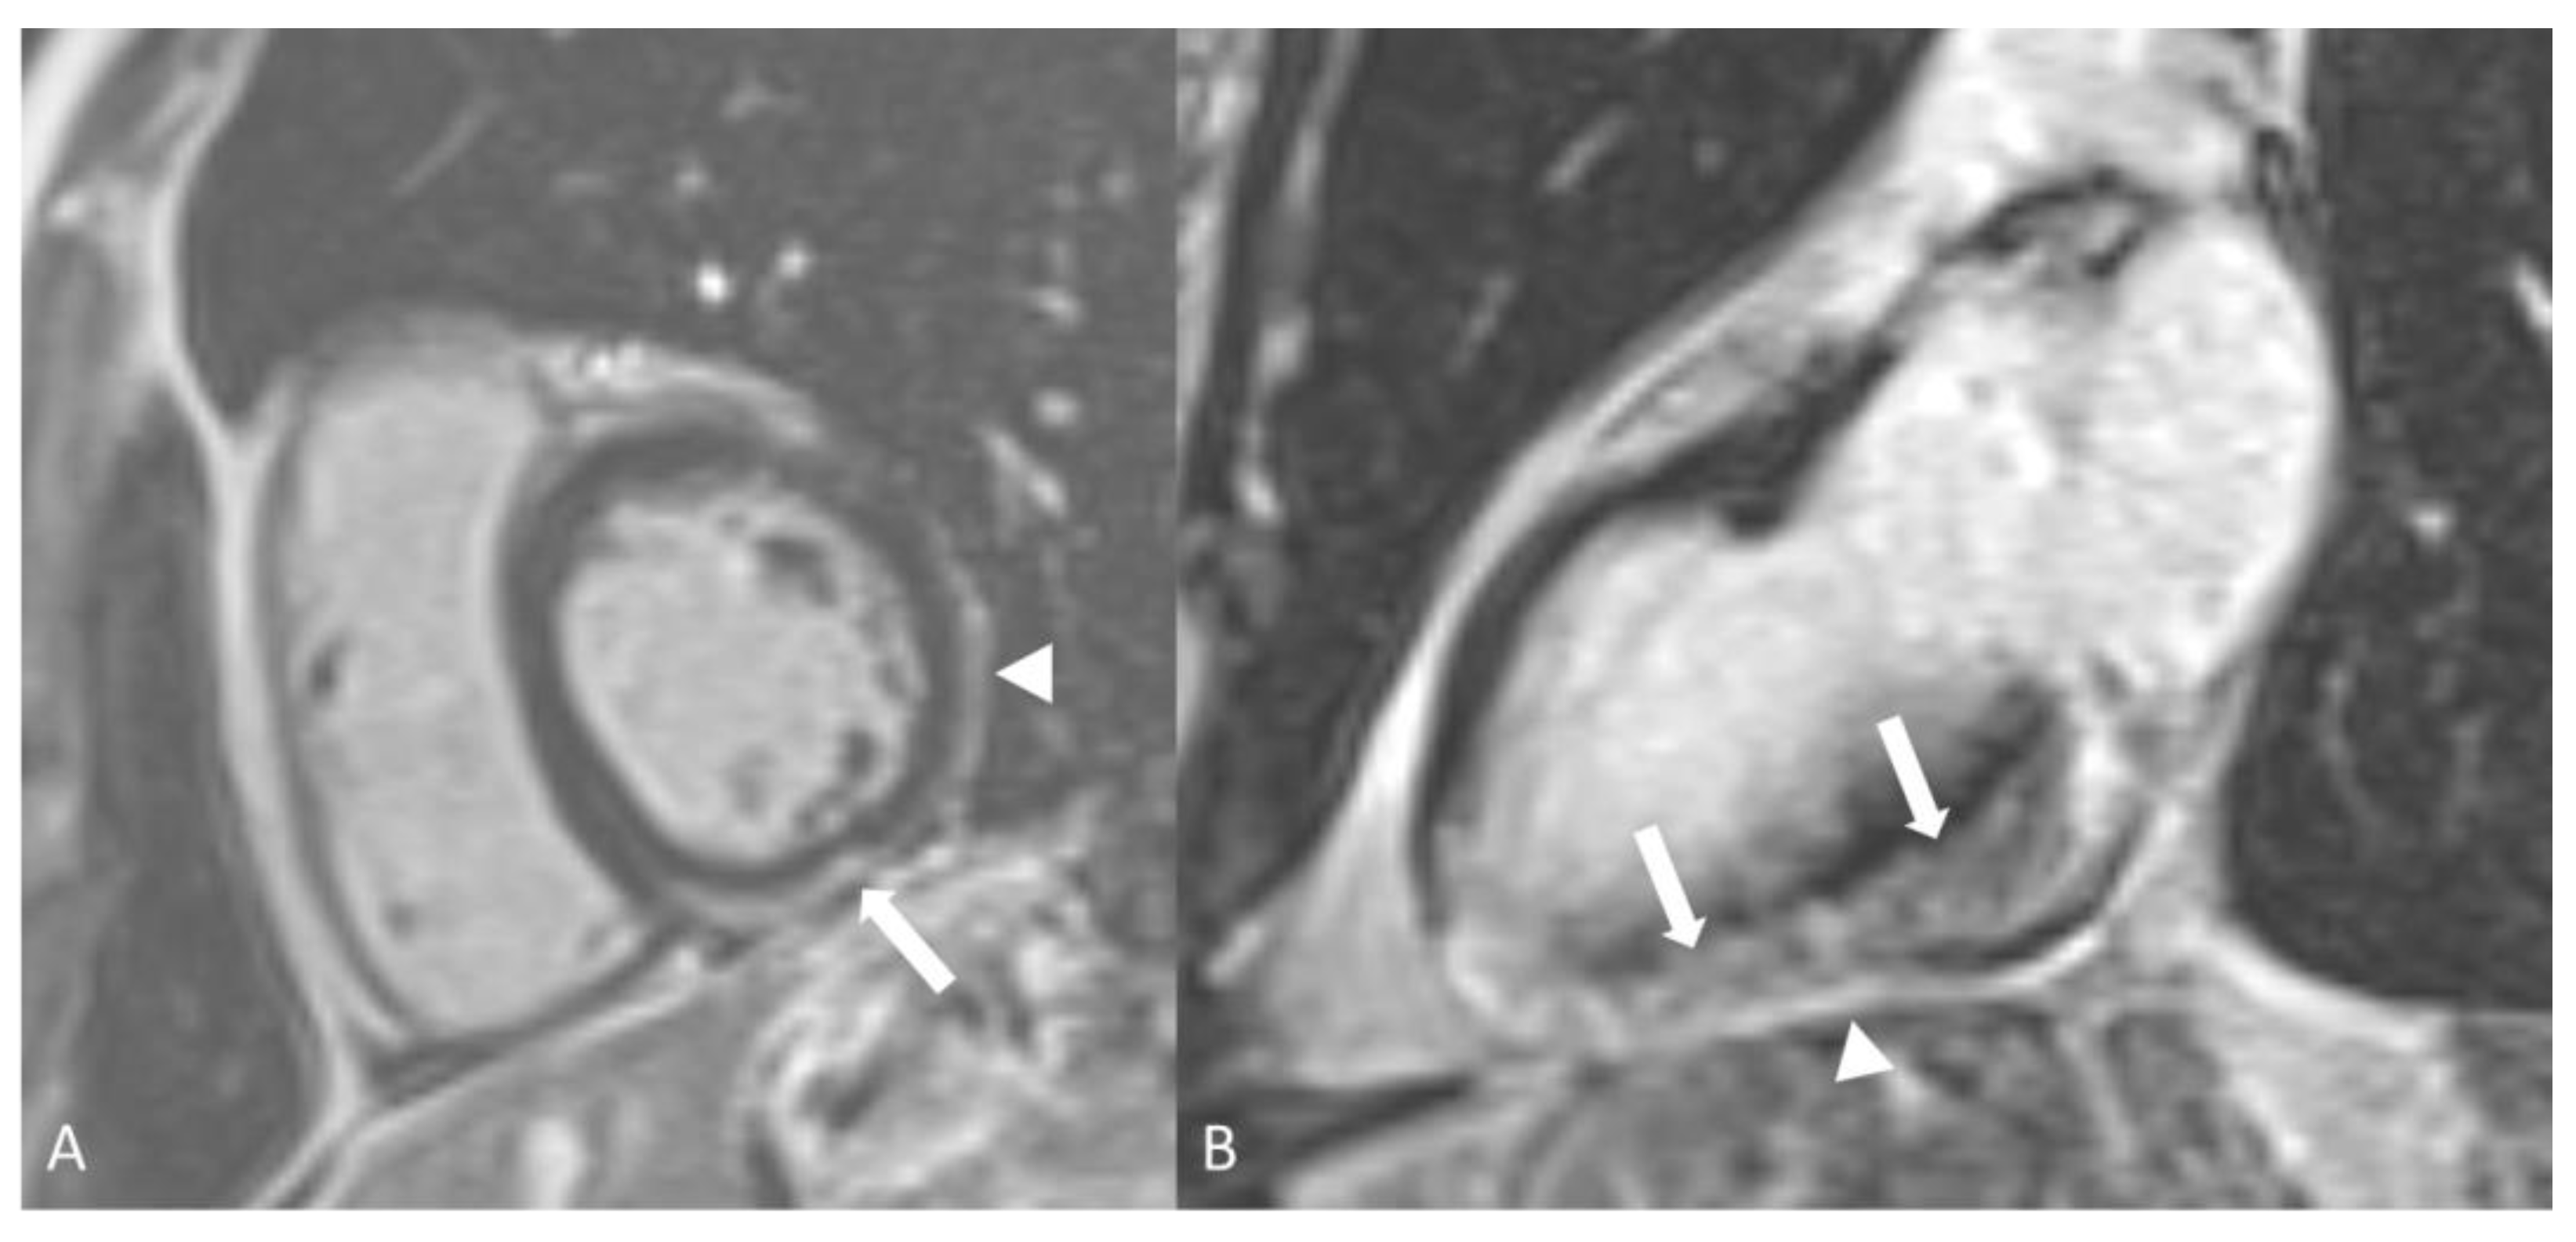

2.3.2. Eosinophilic Granulomatosis with Polyangiitis

- White, J.; Dubey, S. Eosinophilic granulomatosis with polyangiitis: A review. Autoimmun. Rev. 2023, 22, 103219. [Google Scholar] [CrossRef]

- Romero Gomez, C.; Hernandez Negrin, H.; Ayala Gutierrez, M.D.M. Eosinophilic granulomatosis with polyangiitis. Med. Clin. 2023, 160, 310–317. [Google Scholar] [CrossRef]

- Dennert, R.M.; van Paassen, P.; Schalla, S.; Kuznetsova, T.; Alzand, B.S.; Staessen, J.A.; Velthuis, S.; Crijns, H.J.; Tervaert, J.W.C.; Heymans, S. Cardiac involvement in Churg-Strauss syndrome. Arthritis Rheum. 2010, 62, 627–634. [Google Scholar] [CrossRef]

- Zerizer, I.; Tan, K.; Khan, S.; Barwick, T.; Marzola, M.C.; Rubello, D.; Al-Nahhas, A. Role of FDG-PET and PET/CT in the diagnosis and management of vasculitis. Eur. J. Radiol. 2010, 73, 504–509. [Google Scholar] [CrossRef]